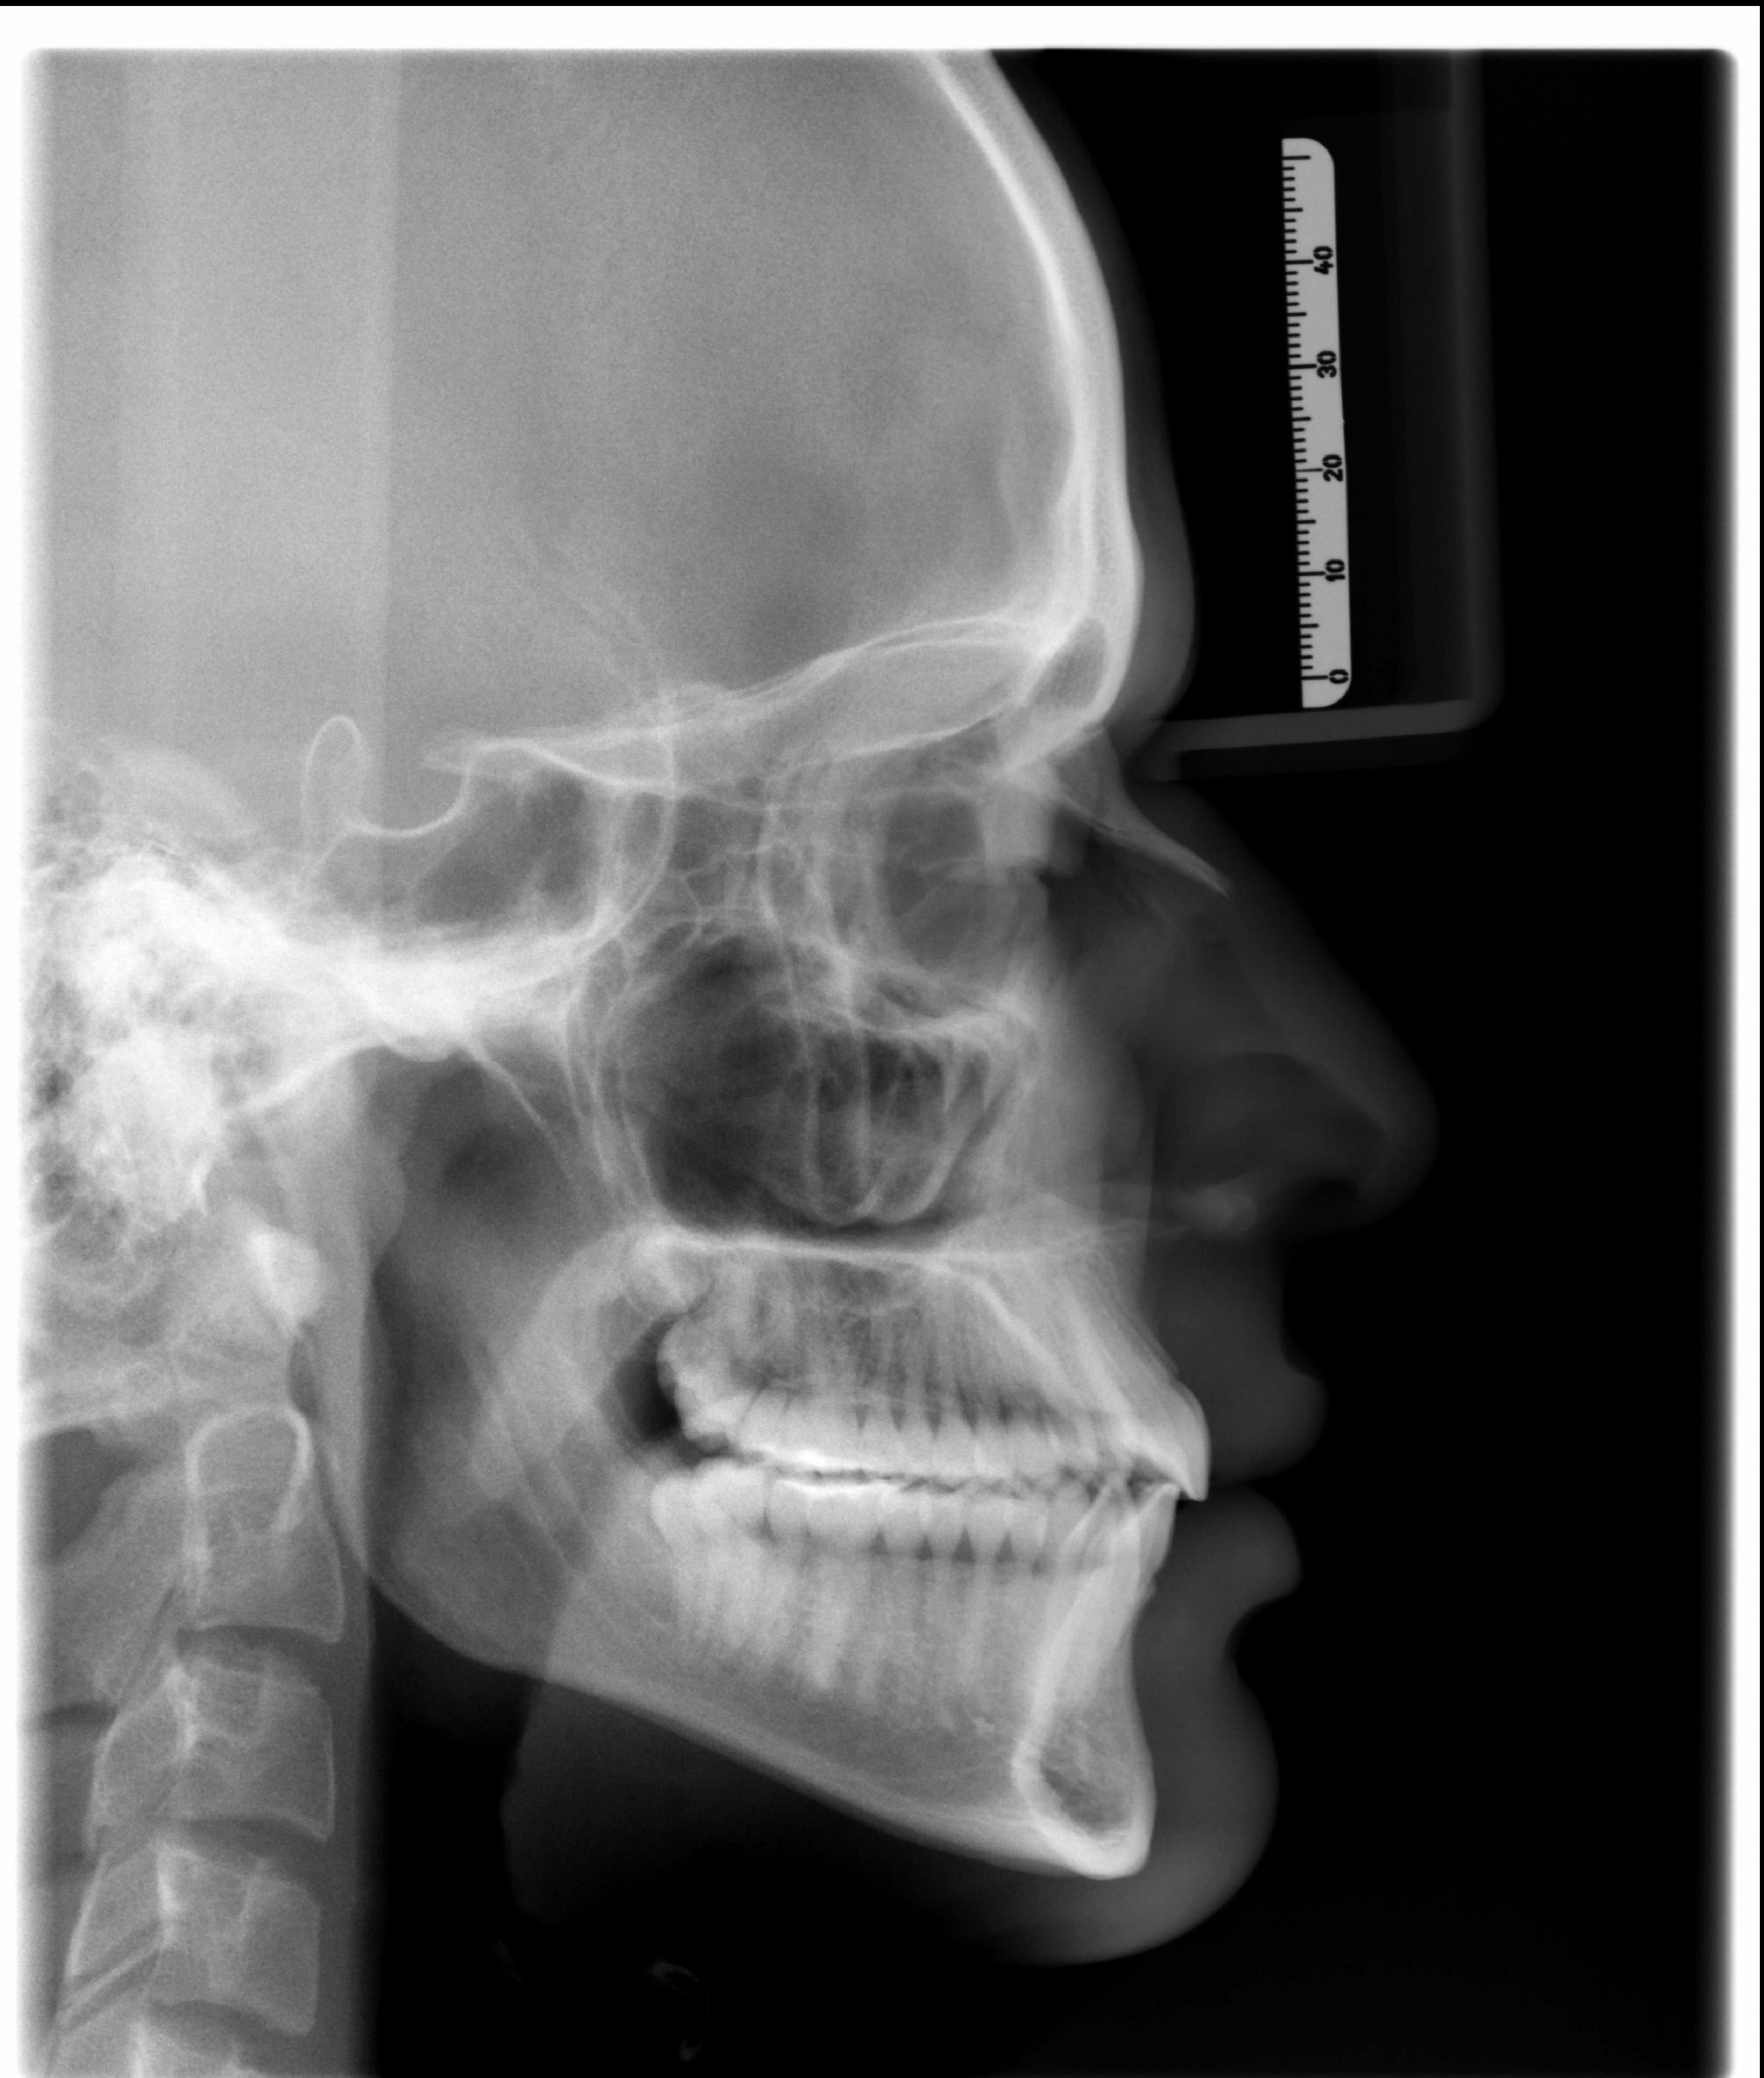

A Radiografia Cefalométrica é o exame no qual se estuda as dimensões das estruturas do crânio e da face. Neste exame, através da medida de ângulos e dimensões lineares é realizado o Traçado Cefalométrico, através de Análises Cefalométricas das quais são planejados diversos tipos de intervenções odontológicas. Sua maior indicação é o planejamento de tratamentos ortodônticos.